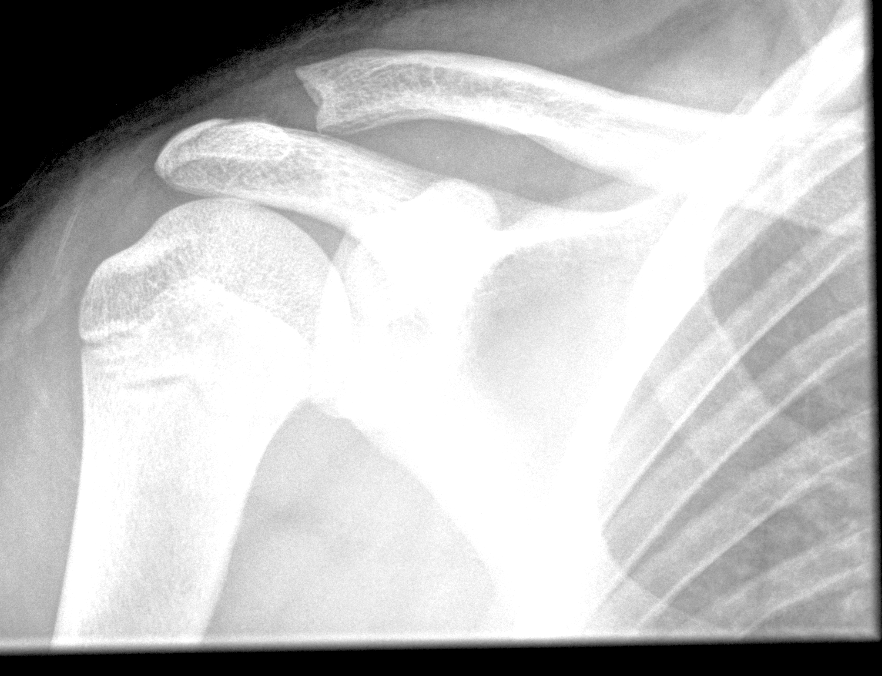

Info Images Findings Impression Reco/Acuity Case Images View Images / Launch Visage Case Notes History 2-month-old presents with decreased right arm movement, increased fussiness, and increased sleepiness for 2 days. Suspected non-accidental trauma. Exam Skeletal survey Prior Study none Dicom View Reference Material

Section 1 Submit Findings CB1550 Findings Skeletal Survey - Technique Check Skull AP/Lat Yes No Cervical and Thoracolumbar spine Yes No Chest X-Ray Yes No Ribs – Left/Right Oblique Yes No Abdominal X-Ray Yes No Pelvis with both hips Yes No Bilateral Humerus, Forearm, Hand Yes No Bilateral Femur, Tibia/fibula, feet Yes No Any additional lateral views of the extremities Yes No The exam is over or under penetrated. Yes No The exam may or may not be limited by overlying structures or soft tissues, body habitus, patient positioning, support devices, or motion. Yes No The area of concern is indicated by the patient, technologist, or care provider. Yes No The area of concern is included on the exam. Yes No Soft Tissues There is soft tissue swelling, indistinctness of fat/muscle planes, gas, or laceration in the area of clinical concern. Yes No There is an effusion, fat pad displacement, or fat fluid level. Yes No There is a radiodense or lucent foreign body. Yes No There are other densities, calcifications, post-surgical changes, or support devices in the soft tissues. Yes No Any support lines/tubes. Yes No Bone There is a break or interruption of the continuity of the cortical or cancellous bone. Yes No There is overriding of the trabeculae with apparent sclerosis. Yes No There is displacement of a fracture fragment. Yes No There is bowing of the bone in addition to the fracture at the apex of the bowed bone concerning for the greenstick. Yes No There is a spiral fracture of the leg concerning for toddler’s fracture. Yes No There is abnormal angulation or bulging of the cortical surface relative to the normal cortex which could be from a buckle or torus fracture. Yes No There is a displaced fragment which may be from avulsion by a tendon, ligament, or joint capsule or from a comminuted or other fracture. Yes No The stress trabeculae or other trabeculae of the cancellous bone are interrupted or otherwise abnormal. Yes No There is subperiosteal or endosteal reaction which could indicate a healing or subacute fracture or other abnormality. Yes No There is hard/soft callus formation. Yes No There is remodeling of the bone. Yes No There is a corner fracture or metaphyseal lesion that could be from nonaccidental trauma. Yes No There are multiple fractures of different ages. Yes No There are vertebral body/spinous process fractures. Yes No There are rib fractures. Location - posterior or lateral. Yes No There is scapular/sternal fracture. Yes No There are fractures of the digits. Yes No There are wormian bones. Yes No There are intrasutural bones. Yes No There is metaphyseal abnormality (lucencies, increased density, erosion) which may be from something other than injury such as stress, metabolic disease (e.g. rickets with loss or distortion of the zone of the provisional calcification), neoplasm (e.g. leukemia), heavy metals, inflammation, or infection. Yes No There are metaphyseal spurs. Yes No There are bony deformities involving multiple bones. Yes No The bones are gracile. Yes No There are non-healing fractures. Yes No There is/are focal or multifocal lytic/lucent, blastic/sclerotic or mixed density lesion(s) or other abnormality. Yes No Overall bone density is increased or decreased with or without thinning or thickening of the cortical or cancellous bone. Yes No Growth plates, ossification centers, apophyses The growth plate(s) is/are abnormal. Yes No There is widening of the physis from a fracture with or without displacement of the epiphysis (Salter-Harris I). Yes No There is a fracture through the physis which then extends into the metaphysis with or without angulation or displacement (S-H II). Yes No There is a fracture through the physis which then extends into the epiphysis and is intra-articular, with or without angulation or displacement (S-H III). Yes No There is a fracture through the metaphysis, physis, and epiphysis which extends into the joint space with or without angulation or displacement (S-H IV). Yes No There is narrowing of the physis from a compression fracture (S-H V). Yes No The apophysis, epicondyle, secondary ossification center, or accessory ossicle is displaced or otherwise abnormal. Yes No The ossification centers are underdeveloped. Yes No Joints and alignment There is an effusion, fat pad displacement, or fat fluid level. Yes No The epiphysis or subchondral bone is fractured, interrupted, flattened, compressed, impacted, displaced, or otherwise abnormal. Yes No There is an intra-articular loose body or chondrocalcinosis. Yes No The joint is widened, narrowed, dislocated, malaligned, or incongruent. Yes No There is pseudoarthrosis. Yes No Other findings There are developmental changes or other anatomic variants or other existing conditions that may or may not be contributing to symptoms which can or should be further evaluated non-emergently or are otherwise incidental. Yes No The remainder of the exam is abnormal for age. Yes No The lungs show focal airspace opacity. Yes No There is pneumothorax. Yes No There is organomegaly. Yes No There is intra-abdominal calcification. Yes No There is displacement of the bowel loops. Yes No There is free intraperitoneal air. Yes No The bowel loops are dilated/obstructed. Yes No There is paraspinal soft tissue abnormality. Yes No